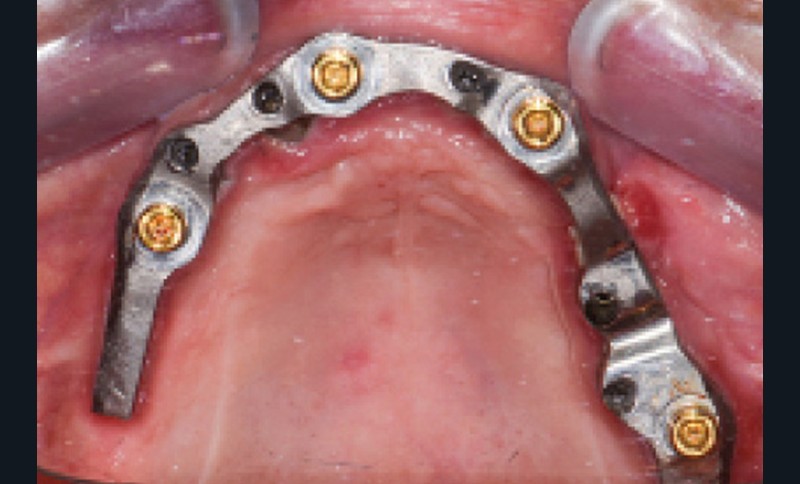

Une réhabilitation par PACSI maxillaire a été réalisée dix ans auparavant sur 5 implants en place de 13, 12, 21 et sur 24 et 26 (fig. 2a et b). Dans le cadre du plan de traitement initial, 6 implants avaient été indiqués. L’un d’entre eux, en position distale dans le secteur I, n’a jamais été ostéointégré. La patiente ne souhaitant plus de chirurgie, il avait donc été décidé de réaliser une prothèse sur 5 implants. La barre est directement connectée aux implants. À la mandibule, la patiente présente également une PACSI sur 2 implants associés à 2 piliers Locator®.

Lors de l’examen clinique, après dépose de la prothèse et dévissage de la barre, le constat est alarmant : présence de plaque abondante…